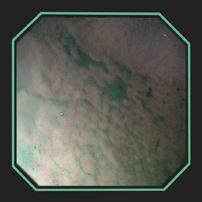

VISUALIZING SLIMER AT WORK

DISTRIBUTION OF SLIMER THROUGHOUT SQUAMOUS AND GLANDULAR REGIONS

DISTRIBUTION OF SLIMER (without color dye) SHOWING PRODUCT GRANULARITY

The above gastroscopy images show Slimer coating the stomach. The horses received 2oz of Slimer via syringe and then lunged at the walk and trot for 10-15 minutes to simulate splashing acid while being ridden. Though Slimer is brown, it was initially dyed blue to be more visible. In order to show that the blue dye did not discolor the stomach or disassociate from Slimer, over 90cc of water was inserted through the gastroscope to “rinse” a portion showing that the underlying tissue remained pink.

DEMARCATION AREA RINSED WITH WATER HIGHLIGHTING SLIMER’S GRANULARITY

DISTRIBUTION OF SLIMER (without color dye) THROUGHOUT SQUAMOUS AND GLANDULAR REGIONS